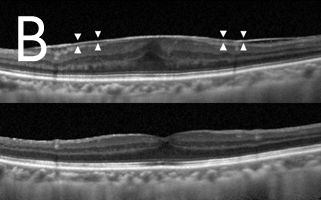

近视超过600度的人士眼球拉长的情况非常严重,黄斑点亦被拉扯变薄。再加上不正常的玻璃体和黄斑点视网膜前膜增生之牵引,导致黄斑点神经组织裂开,甚至丧失视力。如未能及早施行适当治疗,黄斑点裂损有可能进一步恶化,导致黄斑点穿孔和黄斑点视网膜脱落。利用光相干性断层造影可及早发现并作出准确的诊断(图3)。治疗方法是施行扁平部玻璃状体切除术,移除凹前表质玻璃体,并进行气体和液体交换,治疗可治愈大部份病人的黄斑点凹位,而大部份病人在手术後亦无须保持俯卧。

![]() ![]() 图3:光相干性断层造影(OCT):(A)发现大量黄斑点裂损,并有视网膜黄斑点凹位脱落迹象,且在黄斑点凹位附近发现不正常的玻璃体牵引(箭头所指位置)。(B)手术後六个月黄斑点裂损的情况大有改善,减少视网膜黄斑点脱落的幅度。 |